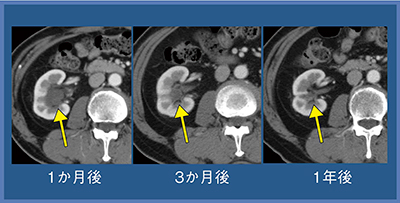

症例1(70歳代,男性)は,腎門部のclear cell RCCである。冠状断再構成画像で,3本のニードルとその周囲に黒くアイスボールが認められる(図2)。腫瘍が黒い範囲に入ったことを確認して治療を終了した。経過観察では,黒く描出された腫瘍部が徐々に吸収され,最終的には同定できなくなった(図3)。

図3 症例1:治療後経過